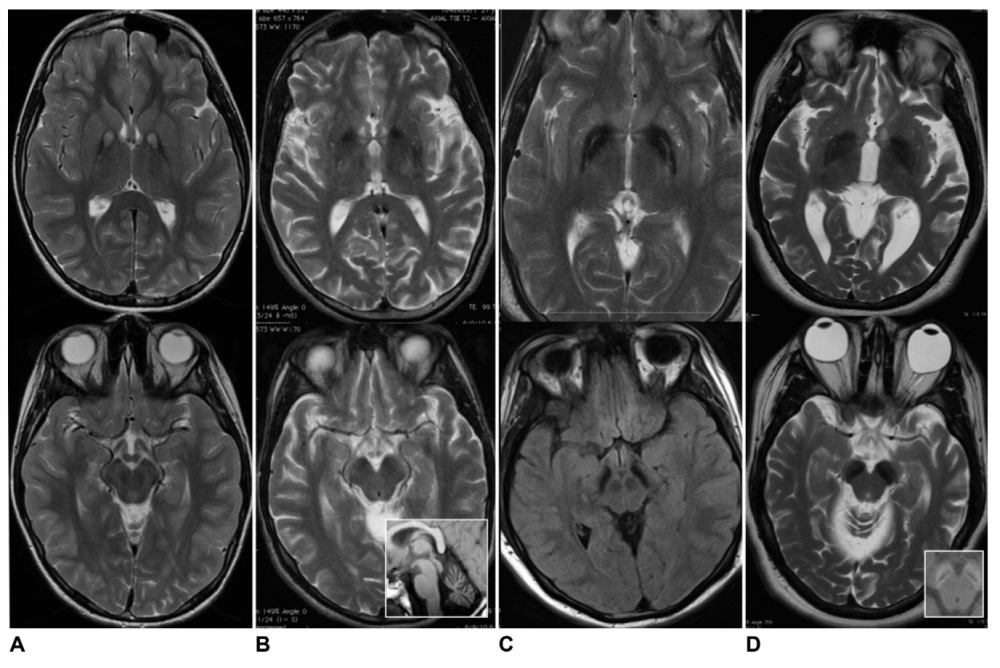

Axial T2-weighted imaging of globus pallidus (top row) and substantia nigra (bottom row):

(A) Pantothenate kinase-associated neurodegeneration;

(B) Phospholipase A2-associated neurodegeneration (inset shows cerebellar atrophy);

(C) Mitochondrial membrane protein-associated neurodegeneration;

(D) Beta-propeller protein-associated neurodegeneration (inset shows T1 hyperintense “halo” in cerebellar peduncles).